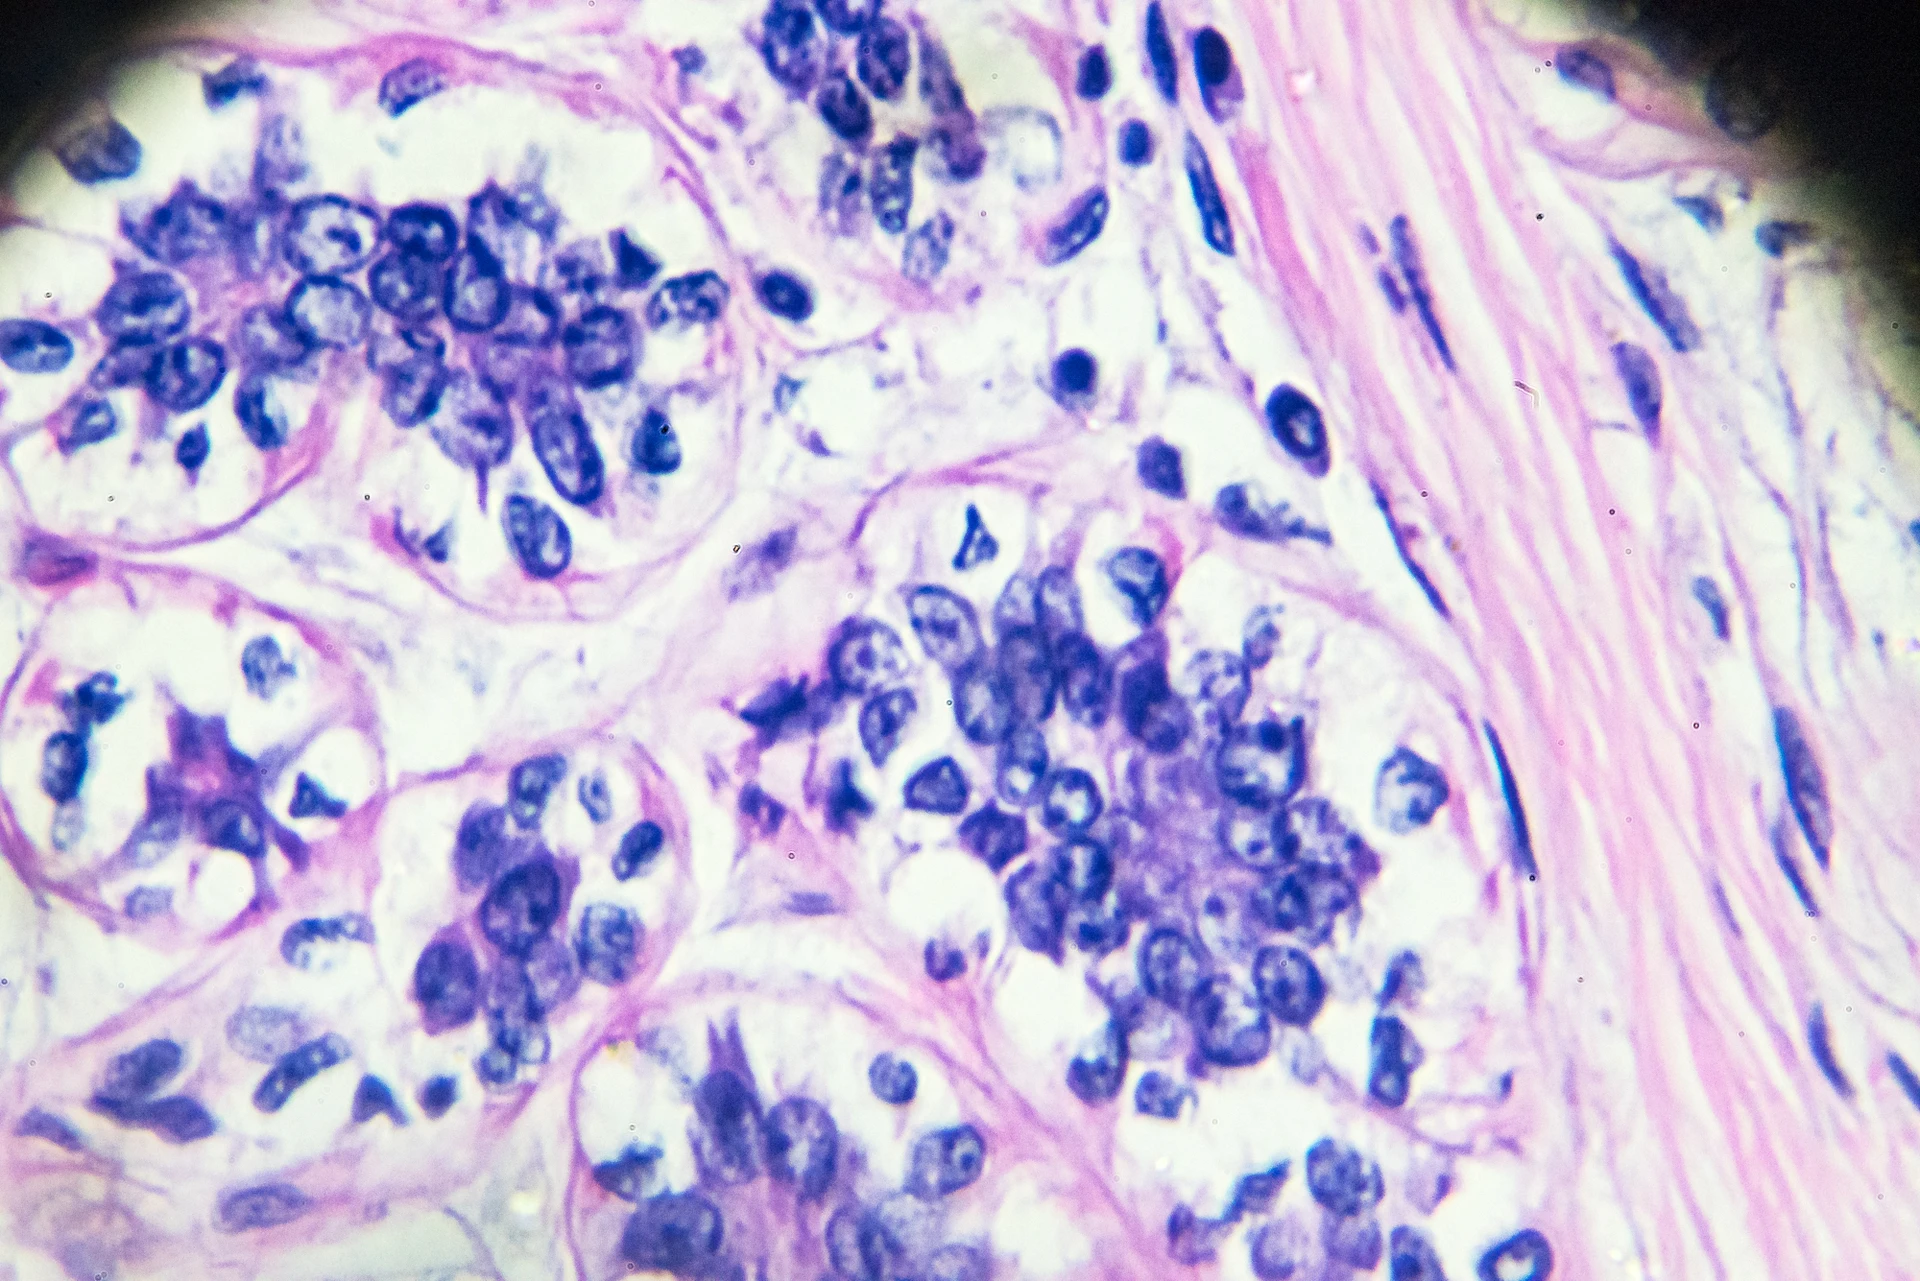

Cancer cells, both immortalized cell lines and primary cancer cells, are invaluable biological tools. They have enabled many significant breakthroughs in oncology research, and continue to be incredibly useful, particularly in the CRISPR era.

What are cancer cell lines?Cancer cell lines are cell lines that consist of “immortal” cancer cells that continually divide and grow over time under laboratory conditions. Human cancer cell lines are most commonly used to study cancer biology, identify new treatments and improve the efficacy of existing cancer treatments.